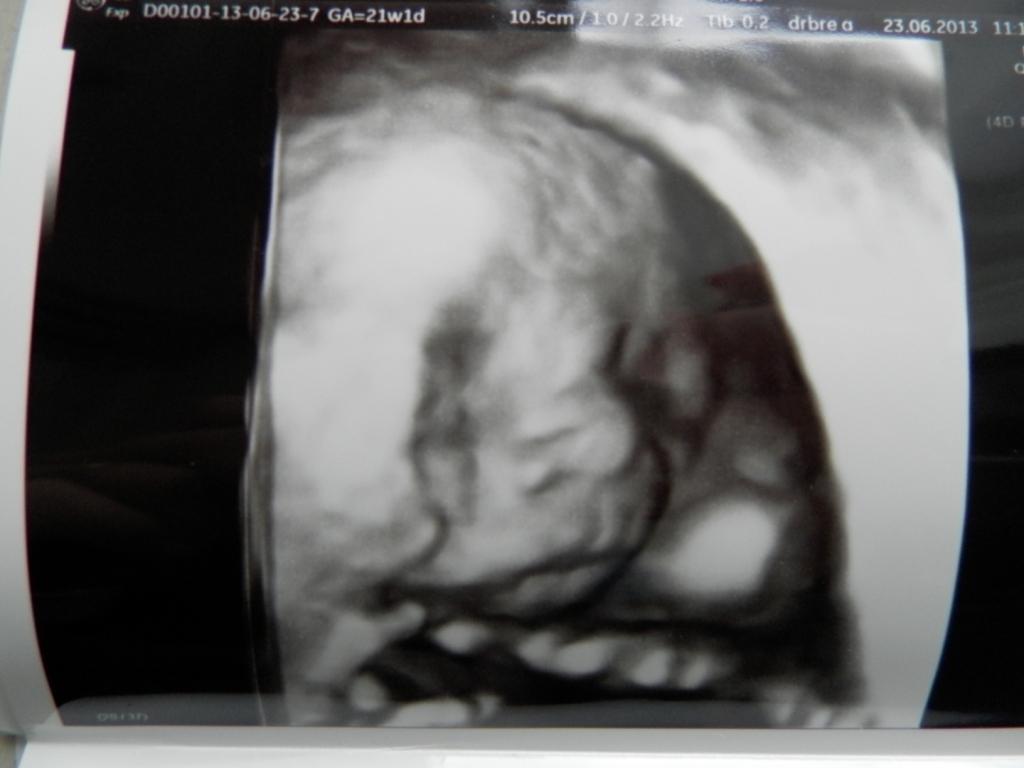

Ešte stále nevieme čo to bude. Či chlapček alebo dievčatko. Som neskutočne zvedavá. Bola som na amnioške a ani tam mi nevedeli povedať. Vraj je otočené riťkou🙂

@kleopatris bola som, no aj tam bolo malinké celý čas otočené riťkou🙂

@kleopatris plodovú vodu mi samozrejme brali. Veď o tom amniocentéza je. No výsledky budú až o 3 týždne. No, teraz už o 2 týždne